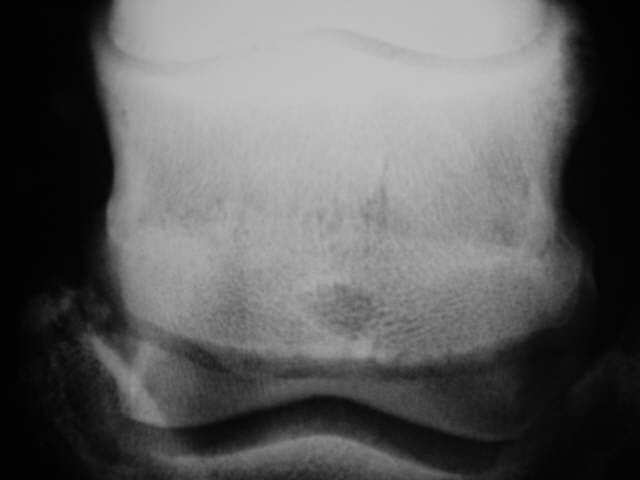

Oseolytische Defekte

Deutliche zentrale Auflösungserscheinung im Strahlbein mit variierender Knochendichte, Zubildungen am oberen und unteren Rand. Röntgenklasse IV